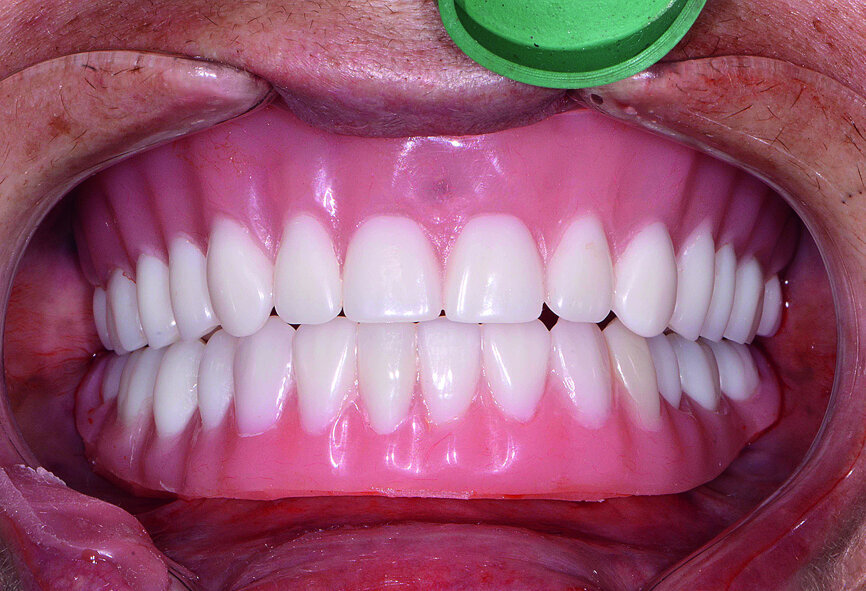

Fig. 21: Post-op retracted open-bite view.

Fig. 22: Post-op retracted closedbite

view.

The final restoration was delivered at the next appointment and established accurate fit, function and interocclusal relationship (Figs. 21 & 22). No adjustments were needed for the monolithic zirconia prostheses because of the PMMA try-in process, which captured the precise modifications needed for proper form and aesthetics. Final radiography confirmed complete seating of the BruxZir restoration on the Inclusive Custom Implant Abutments. The patient was extremely happy with the reconstruction of her maxillary and mandibular arches, which restored aesthetics, dental function, comfort and confidence.